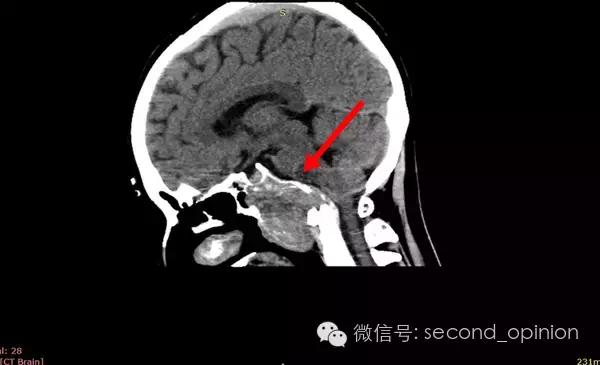

患者自2013年6月起无诱因出现吞咽困难,伴吐字不清症状,自觉舌肌无力一个星期,偶有头痛发作,不伴呛咳,呕吐,无抽搐发作。当时耳鼻喉科做相关检查,咽部无异常表现。行头部CT检查发现颅内占位,范围约43*30mm。保守治疗,后病情稳定,未发现症状明显加重。

至2014年1月,出现左耳耳鸣,表现为低调杂音,未发现听力明显降落,偶有脸部麻木,无面瘫。行MRI检查,颅内占位范围约60*45*47mm。2014年2月2日第一次手术,行内镜导航下经蝶窦颅底肿瘤切除术,切除体积约50*45*50mm,手术顺利,术后头痛症状消失。左耳低调耳鸣术后消失两周后再次出现,右耳术后出现偶发轻度耳鸣。2014年5月4日第二次手术,行内镜口鼻蝶入路脊索瘤切除术,切除肿瘤体积45*40*50mm,过程顺利,术后耳鸣消失,病情稳定后出院。

2014年6月15日 进行射波刀放疗,32.5Gy/5fx,剂量曲线69%包绕,治疗期间对症脱水,减轻放疗反应,完成全部治疗后出院。

2014年12月 进行质子放射治疗。

2014年9月1日MRI(手术治疗前)

质子治疗前